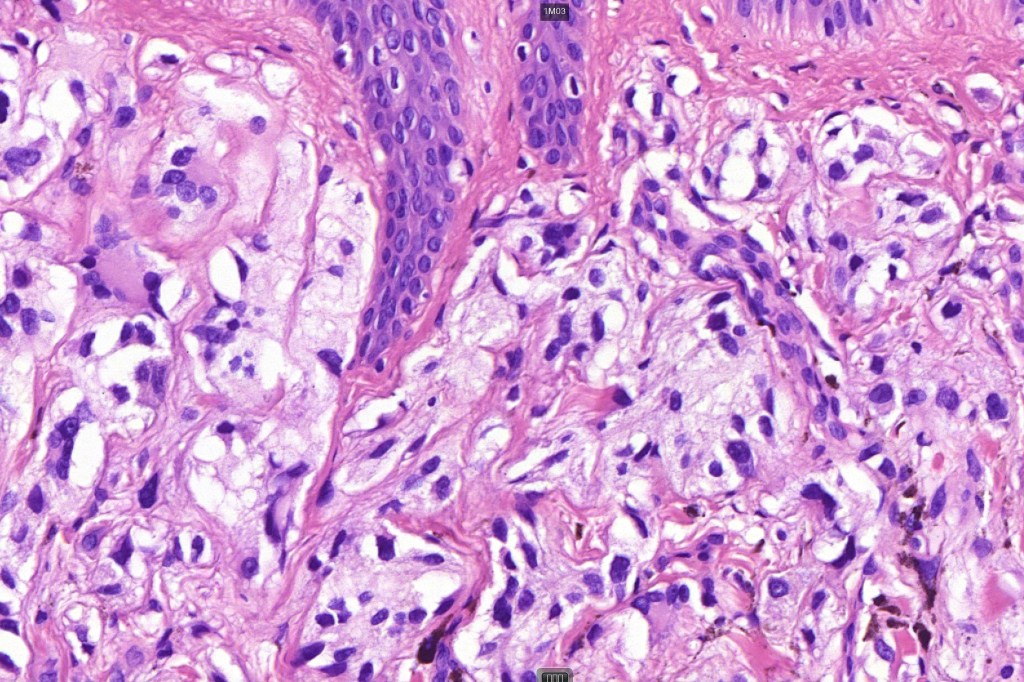

•Superficial epithelioid cells

•Deep spindle cells

•Focal atypia (enlarged, hyperchromatic nuclei)

•Clear cells

•Dendritic cells

•Melanophages

•Multinucleate giant cells

• Cytoplasmic intranuclear pseudo-inclusions, small eosinophilic nucleoli

•Occasional mitoses